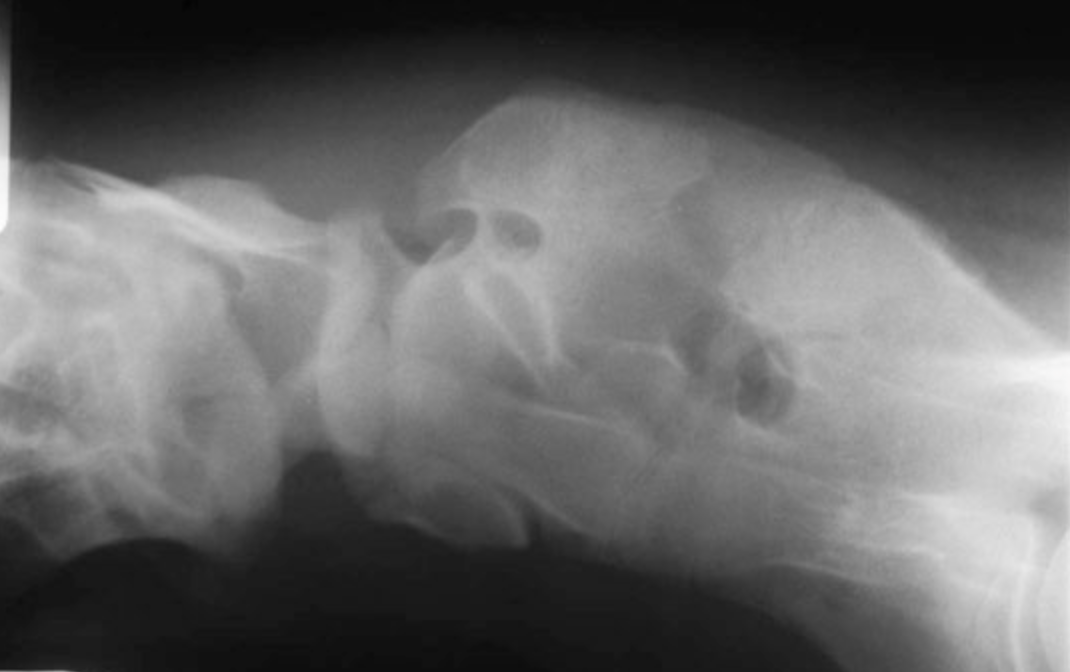

Whats the diagnosis?

Which breeds are most commonly affected?

What is the treatment?

OAAM - various abnormalities incl absence of a dens, hypoplasia of atlas, fusion of the atlas to occiput

Arabs most commonly affected - familial, do not breed

No treatment really

CSs - still birth, progressive ataxia, occasionally only restricted neck movement